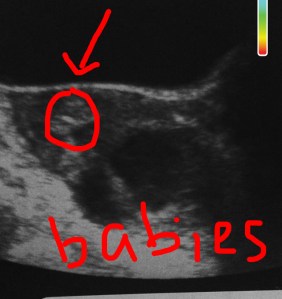

My doctor then inserted the catheter up through my cervix into my uterus (no pain this time, so the cervical dilatation did its job!) and found the best spot to deposit my babies. Once the optimal spot was found, the embryologist sucked up the embryos one at a time (still on screen) and brought them to my RE who then inserted them into another catheter that was woven through the first catheter. We were able to see the catheter on the ultrasound and then BAM, both embryos were transferred right into the top of my uterus where I hope and pray that they will make a home. My mom cried a bit, and I almost did. I have since cried a few times.

I have to say that science is pretty darn cool! I now have two little embryos hanging out in my womb. I call them Thing 1 and Thing 2, and I have been talking to them daily. We were given a picture of both babies as well as the ultrasound to take home and they are currently hanging on my fridge. It makes me feel like I am really pregnant, having an ultrasound on my fridge like most normal woman TTC.